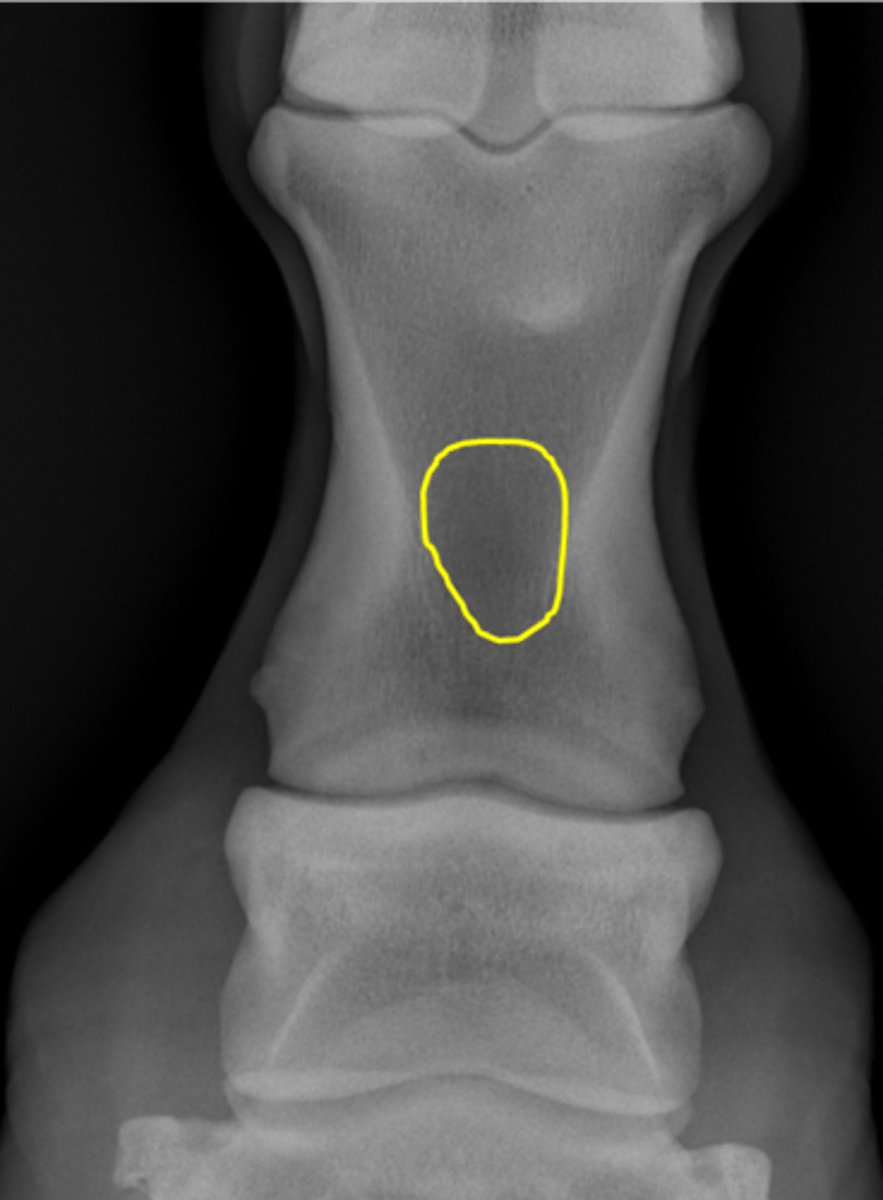

Navicular bone

Proximal border

Flexor surface

Distal border

Articular border

Navicular bone

Flexor cortex

Navicular bone

Proximal border of navicular bone

Distal border of navicular bone

Synovial invaginations